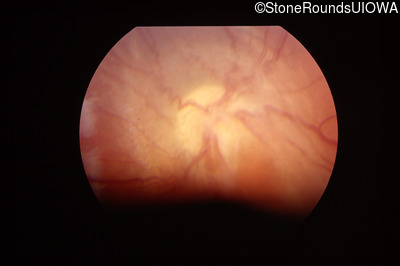

Fundus Photography - Left - 20/32 -1

Exemplar